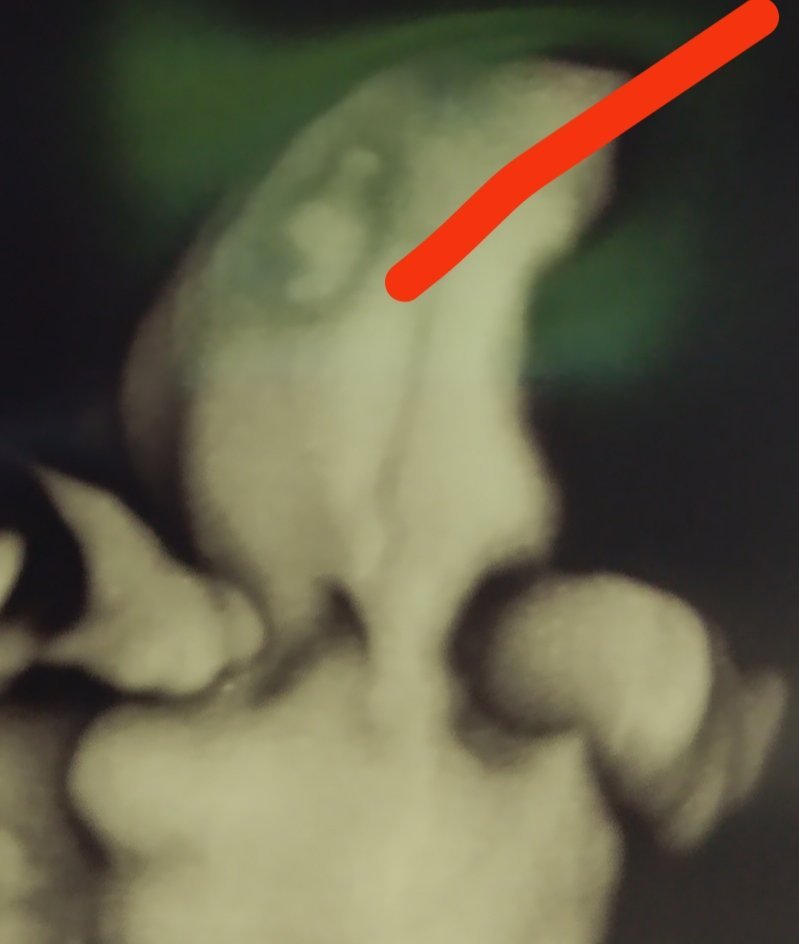

Какво представляват белите точки в плодния сак на ехографската снимка?